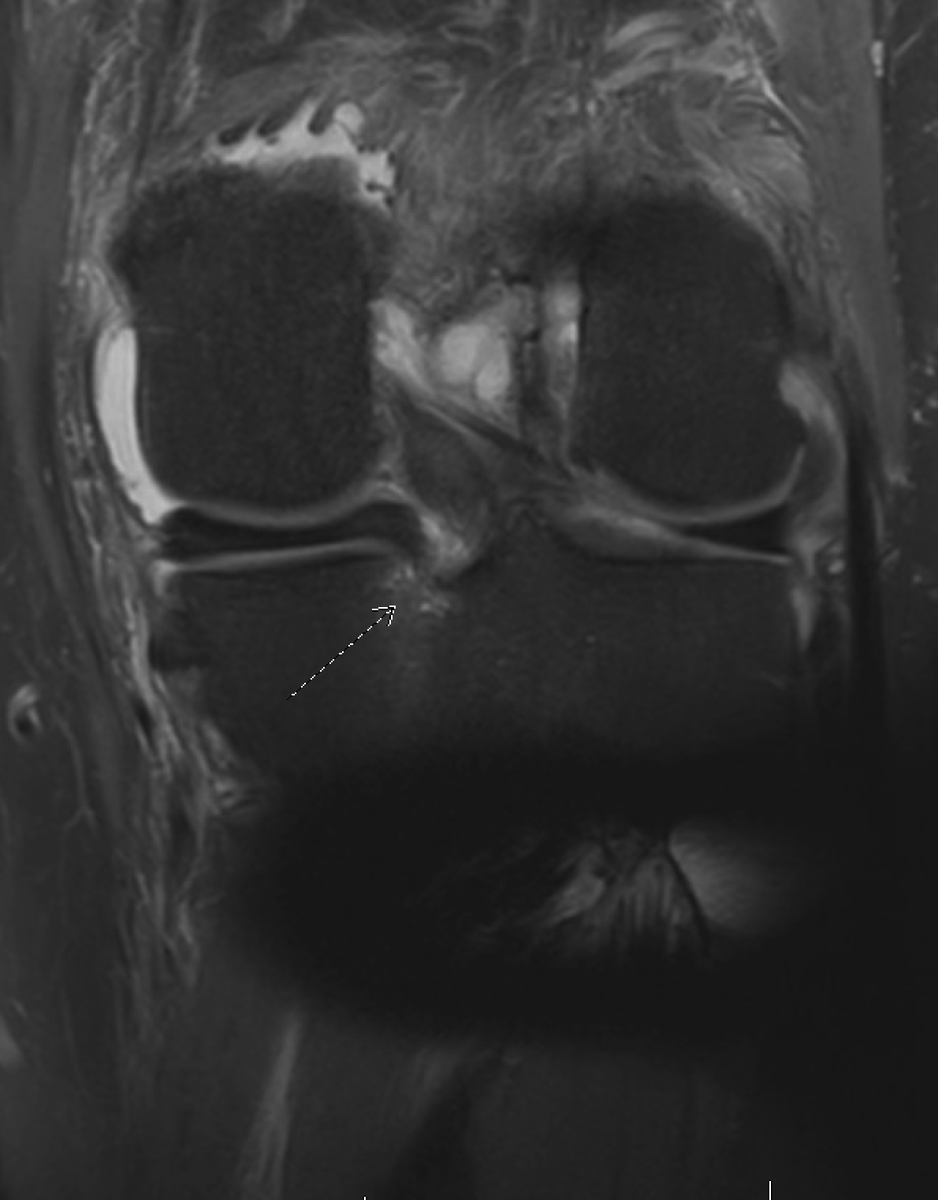

@DanielLiechtiMD Interesting. I’m kinda convinced that extrusion is one of, if not the last thing to occur. Can’t prove that tho. Just makes the most sense in my head.

@SSittonMD I like the idea of first extrusion -> failure of MT ligament -> failure of the root with that edema secondary to increased tension.

Interesting phenomenon: I call this the "pre" root tear with increased tibial signal but intact meniscus root.

When I see a patient that fits the demographics of a meniscus root tear with large knee effusion and posteromedial pain, I am more aggressive with MRI's. Have been seeing more of these as a result.

Have had good success in treating these with restricted weightbearing alone. (with permission)